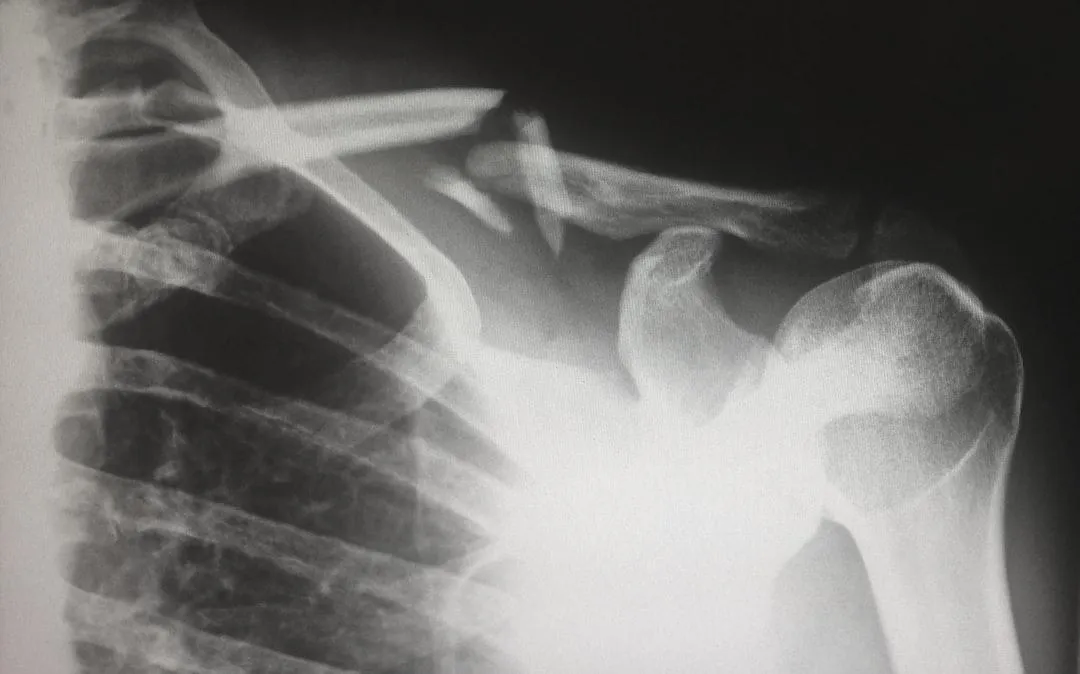

Tipos de fracturas más comunes

Existen varios tipos de fracturas según la forma y el mecanismo de la ruptura.

Algunas formas típicas son:

Fractura abierta (o compuesta):el hueso atraviesa la piel, lo que aumenta el riesgo de infección.

Fractura conminuta:el hueso se rompe en varios fragmentos.

Cómo se diagnostica y trata una fractura

El diagnóstico habitual de una fractura comienza con la exploración clínica y se confirma con radiografía; en casos más complejos se pueden usar TAC o resonancia.